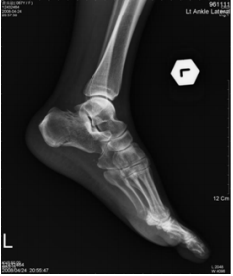

49 27 歲女性患者穿高跟鞋於樓梯間不慎扭傷足部,旋即發生嚴重之腫脹。其 X 光檢查發現為瓊斯氏撕 脫性骨折(Jones fracture),請指出其發生之部位為圖中何處?

(A)甲 (B)乙 (C)丙 (D)丁